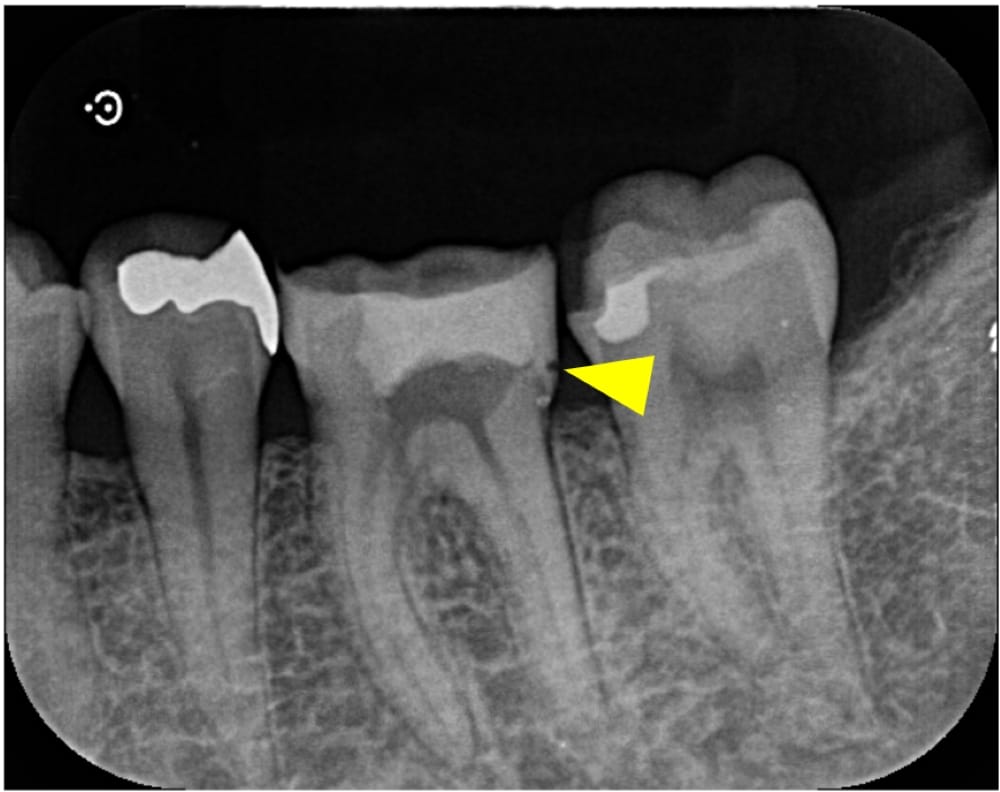

左下6番は仮封がされている状態であり、レントゲン画像では歯と封鎖材料の隙間がある状態でした。口腔内の所見からも、虫歯が残存していることが推測されました。痛みの原因としては、複数回のペリオドンの使用に加え、ラバーダムがない根管治療を受けていることや虫歯が残存していることなどが考えられます。